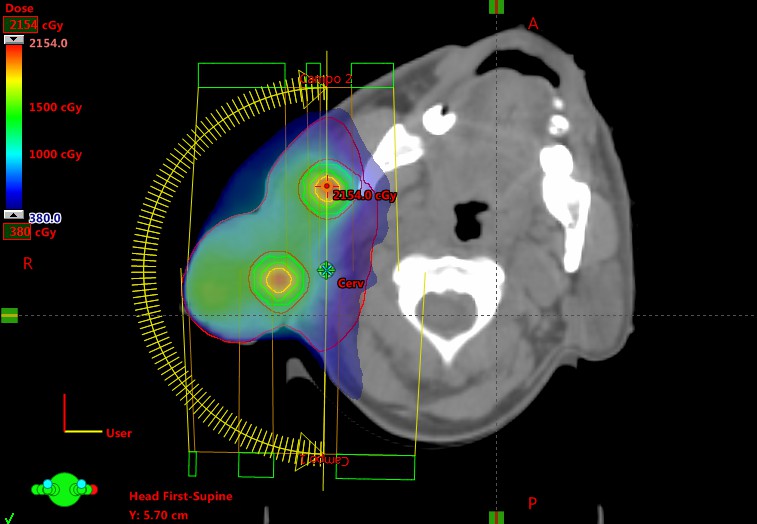

TRATAMENTO DE PACIENTES COM CÂNCER

Ao longo do tempo, o conhecimento sobre a doença foi ampliado, ganhando contornos personalizados. Estamos na Era da medicina de precisão e a cirurgia também se faz presente nesse contexto. Dentre os protagonistas desta história estão expoentes como o cirurgião oncológico, ADEMAR LOPES, uma das maiores referências da América Latina e do mundo em cirurgia oncológica.

“A Oncologia é a especialidade do momento e do futuro. É uma abordagem multidisciplinar, envolvendo cirurgia, radioterapia, quimioterapia, imunoterapia e hormonioterapia, sendo que a cirurgia deve estar no coração do planejamento terapêutico de um paciente com câncer”.Ademar Lopes